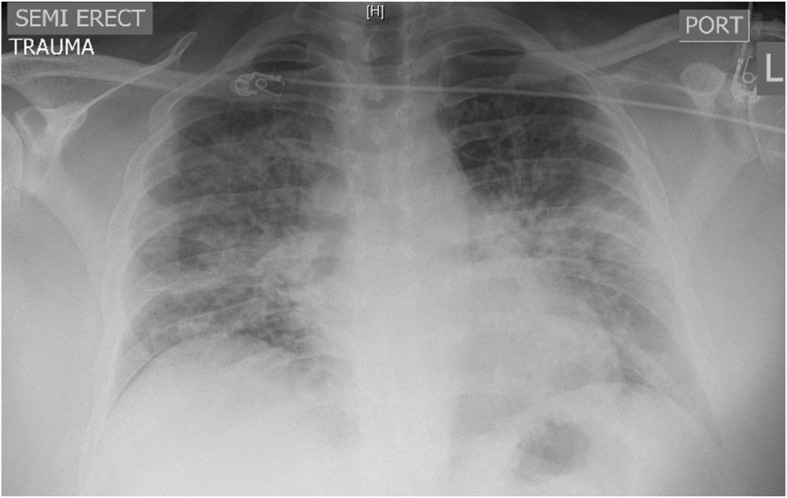

Although abnormalities are frequently found on chest imaging, the findings are non-specific and variable. In the Illinois/Wisconsin cohort, 83% were found to have abnormalities on chest radiograph and 100% were found to have abnormalities on Computed Tomography (CT) of the chest [ref. 15]. A chest x-ray should be obtained in patients with e-cigarettes use who present with respiratory, GI, or constitutional symptoms. Typical of findings on chest radiograph of EVALI is diffuse hazy bilateral opacities with occasional subpleural sparing (Fig. 1). Involvement of all lung lobes can be seen, but is not universal. Additionally, increased interstitial markings can be seen characterized by Kerley B lines. A CT chest should be pursued if there is high suspicion for EVALI but the chest radiograph is normal given the improved sensitivity of CT and/or to assist in ruling out other etiologies. While imaging findings are variable in EVALI, typical findings on chest CT are bilateral ground glass opacities (Fig. 2). Additionally, upper lobe predominant centrilobular nodules are often seen on chest CT [ref. 44]. Since findings on chest imaging are non-specific, other etiologies of lung injury should be considered.